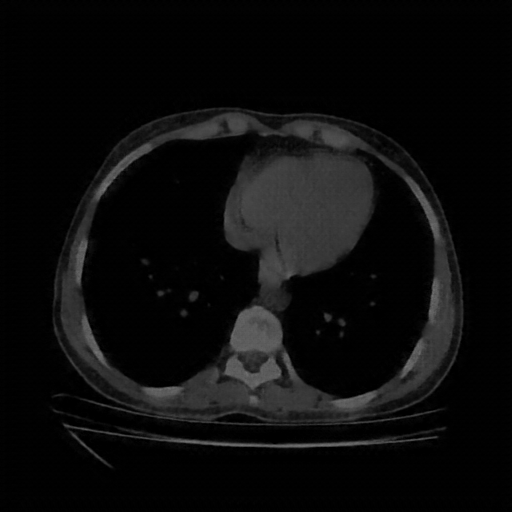

Slice 70 Targeting Evaluation

Slice: Slice_70

Conversion: NATIVE β†’ VENOUS

Generated VENOUS CT scan (A→B translation)

No window - Raw intensity values